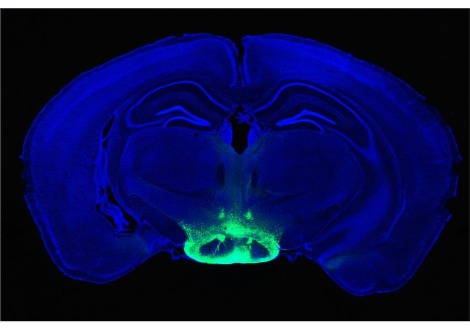

يمكن أن تُسبب الحصبة أيضًا تلفًا طويل الأمد للجهاز المناعي. بعد الإصابة أو التطعيم، تحتفظ الخلايا المناعية المعروفة باسم الخلايا التائية والخلايا البائية والخلايا البلازمية بذاكرة هؤلاء الغزاة، كما يقول ستيفن إليدج، أخصائي المناعة في مستشفى بريغهام والنساء في بوسطن. "تشارك الخلايا البائية في صنع الأجسام المضادة. في الواقع، لا تُفرز أجسامًا مضادة. إنها تتمايز إلى خلايا البلازما، وتصبح هذه الخلايا مصانع الأجسام المضادة. تنتقل إلى نخاع العظم، وهناك تبقى طوال حياتك. يمكن أن تعيش لمدة 30 إلى 40 عامًا، طوال الوقت تُضخّ ذاكرة العدوى،" كما يقول. "اتضح أن الحصبة يمكن أن تقتل تلك الخلايا... إنها تقتل الخلايا التائية والخلايا البائية. إنها تقتل خلايا البلازما."

ويقول إليدج إن 10 إلى 20% من المصابين بالحصبة لديهم ذاكرة مناعية للعدوى أو التطعيمات الأخرى. قد يجعلهم ذلك عرضة للأمراض في المستقبل حتى لو كانوا قد أصيبوا سابقًا أو تلقوا لقاحات ضد البكتيريا والفيروسات.

ويضيف إليدج: "لقد أظهرنا أن هذا يحدث لدى البشر وفي تجارب مُحكمة على قرود المكاك، لذا فهو صحيح لا يمكن إنكاره. وعلم الأوبئة يدعمه بنسبة 100%."